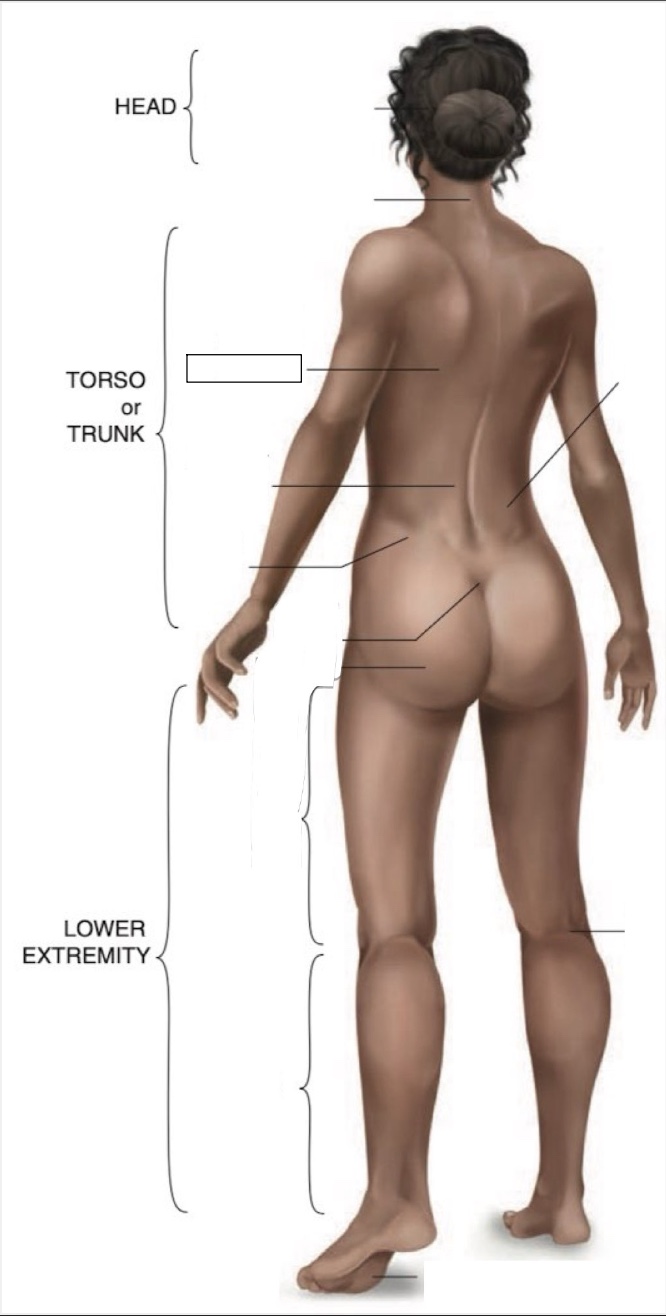

Occipital region

Cervical region

Inferior angle of scapula

Lumbar region

Iliac crest

Sacral region

Buttock

Flank

thoracic region